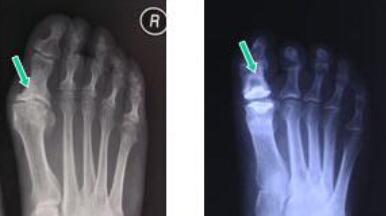

刘先生3年前开始出现脚趾关节疼痛,开始时疼痛持续一周之后就消失了,三个月过后,刘先生疼痛突然发作,发作时疼得无法下地行走。,刘先生马上去到医院检查,医生告诉他是痛风,需要住院接受治疗,然后他只...[详细]

王怀庆主任为他做了一个详细的检查:间断性第1跖趾关节疼痛2年,双足跖趾肿痛,左足第1跖趾关节疼痛加重,双肘肿痛,右肘可见0.5cm大小肿块,双腕、双手、双膝也呈不同程度肿痛现象,夜间疼痛最重,患者不能...[详细]

刘先生到郑州痛风风湿病医院就诊,王怀庆发现刘宇的检查报告显示:刘先生血尿酸629mol/l,高于临床上的正常标准。而且还发现到刘先生大脚趾处肿痛明显,脚跖趾关节红肿,压痛。浮髌试验阳性。针对于刘先生的...[详细]